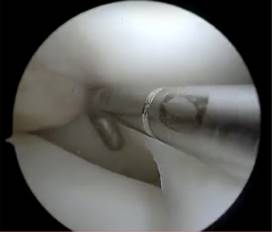

Durante la artroscopía de la rodilla derecha, se encontró una lesión compleja en el menisco medial, que fue diagnosticada como un menisco discoide. Además, se observó una abundante sinovitis y Hoffitis, así como la presencia de una banda fibrosa en la parte ventromedial (Figuras 3 y 4). Se realizó una plastía del menisco medial mediante saucerización y se determinó que el menisco medial estaba estable, por lo que no se requirió el uso de suturas meniscales (Figuras 5 a 7). También se realizó la resección de la banda fibrosa, sinovectomía y Hoffectomía.

Figura 3: Visión artroscópica donde se muestra la cobertura total del platillo tibial medial por el menisco discoide medial.

Figura 4: Visión artroscópica de ruptura de menisco discoide medial durante la realización de artroscopía diagnóstica.